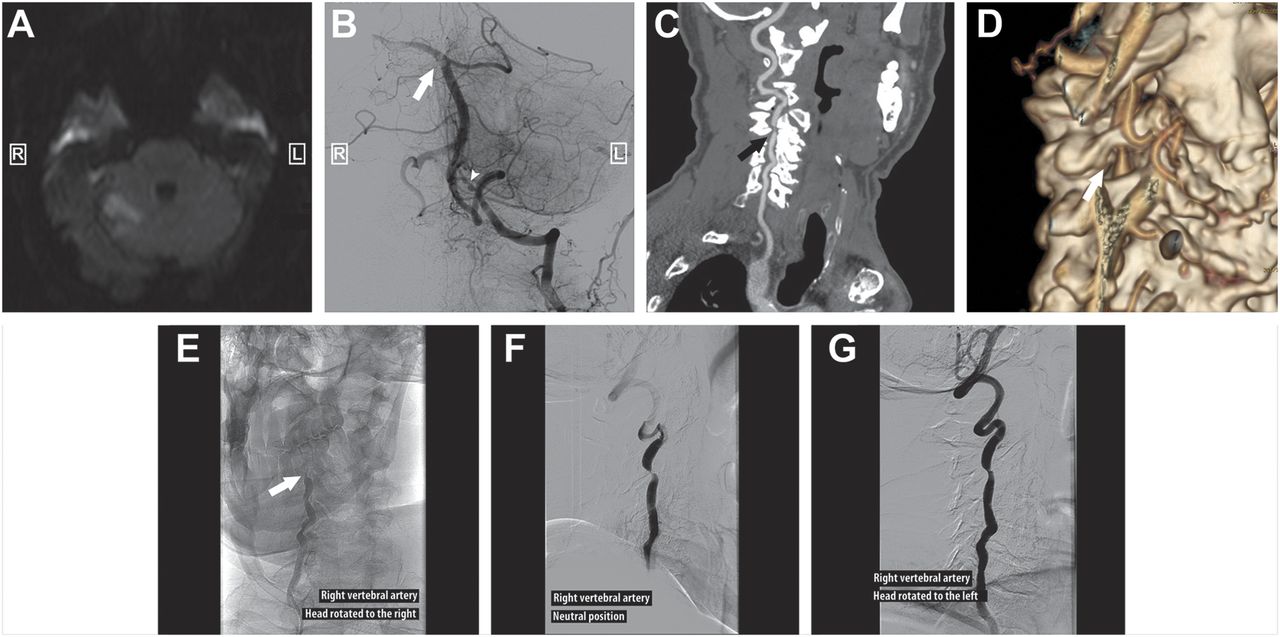

一个77岁的老人提供2次醒来vertebrobasilar缺血的症状(图中,A和B6个月内)。CT血管造影显示缩小右侧椎动脉由于外在压缩的骨赘上第四颈椎关节突妥协transversarium孔(图中,C和D)。动态造影显示间歇性与头把相关的血管闭塞(图中,eg)。后复发,手术减压椎动脉。外在的按压椎动脉是罕见的。1最常见的症状是vertebrobasilar不足。手术治疗保守治疗失败时提出了。1

(一)Diffusion-weighted MRI:对小脑梗塞。(B)血管造影在紧急第二集vertebrobasilar缺血后血栓切除术过程。的形象暗示栓子是顶部的基部的动脉(白色箭头)。操纵一个医源性血管痉挛由于血管内也可见在相同的图像(箭头)。CT血管造影(C)和三维重建(D)。动态造影:完成对椎动脉闭塞的头向右旋转(E);适度压缩头在中立的立场(F)或左旋转(G)。